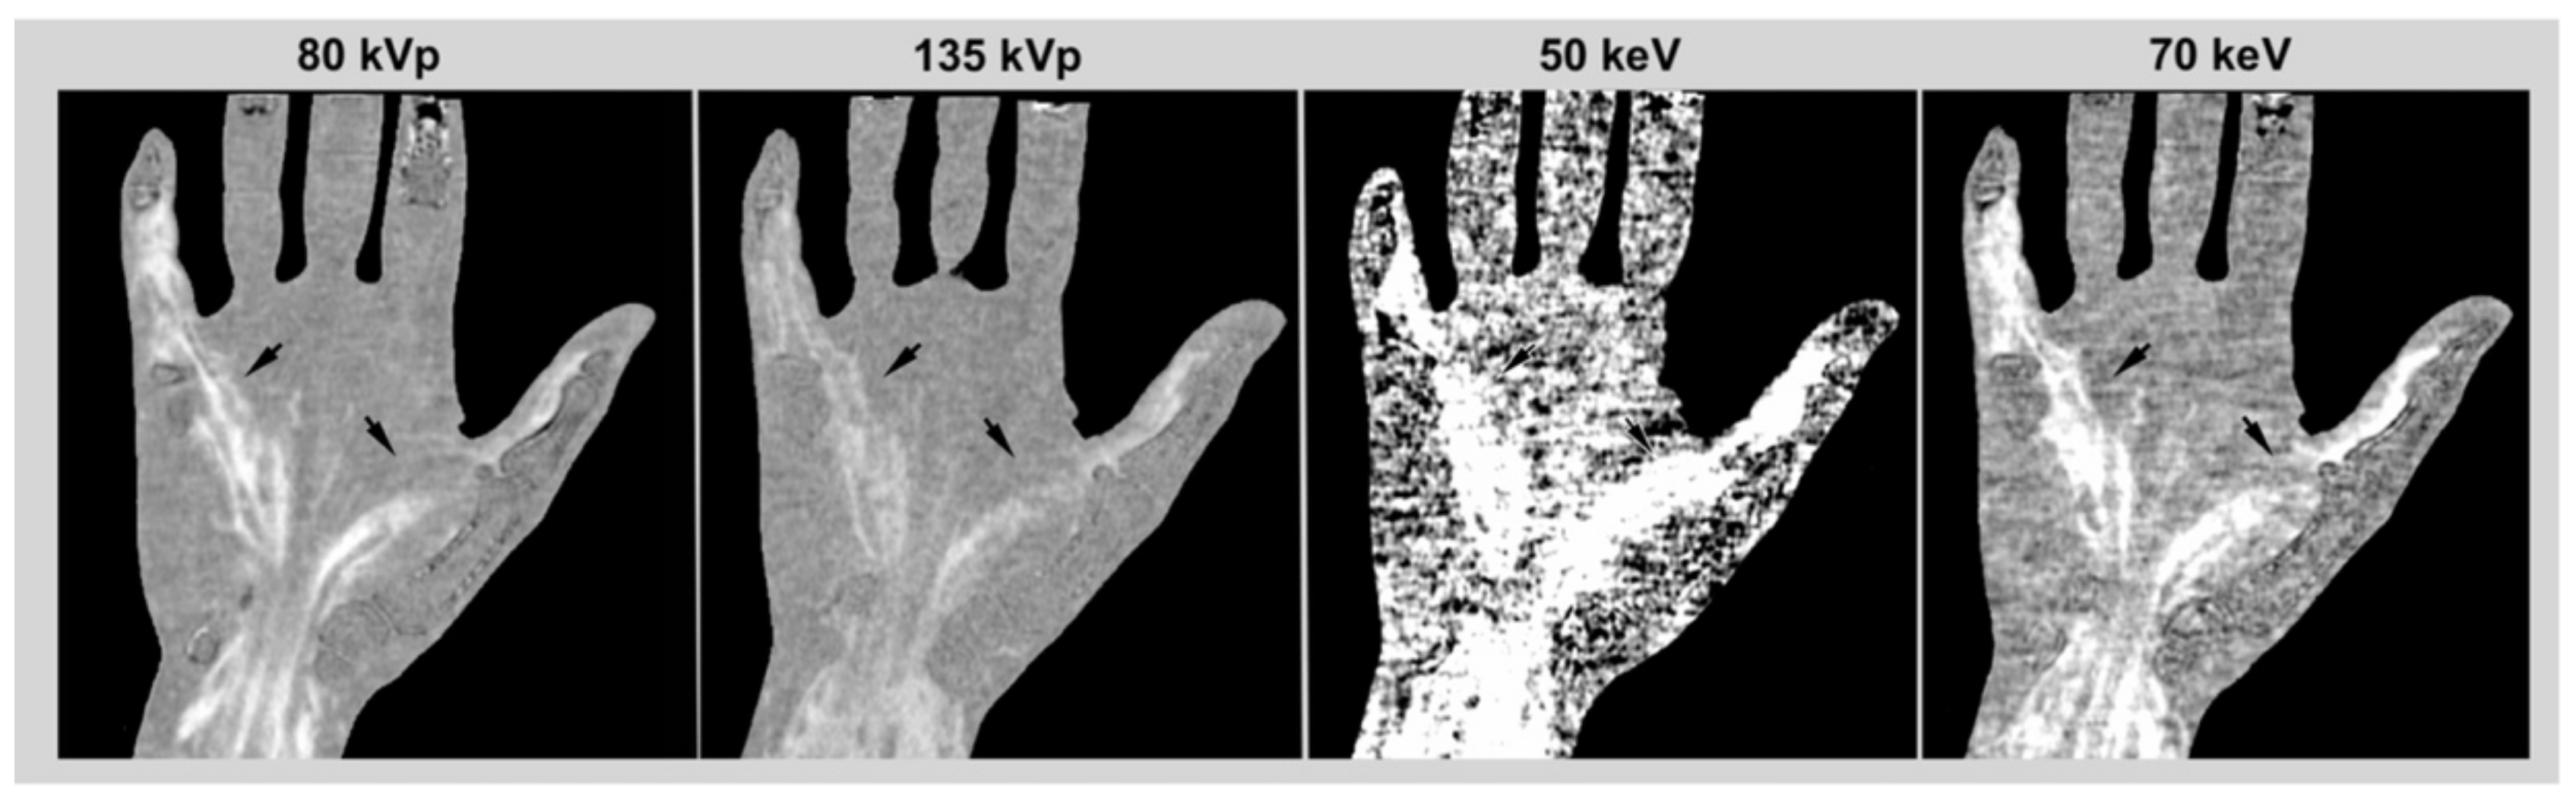

2.3. VMI and Subtraction

2.4. Image Reading

3.2. Image Reading and Statistical Analysis